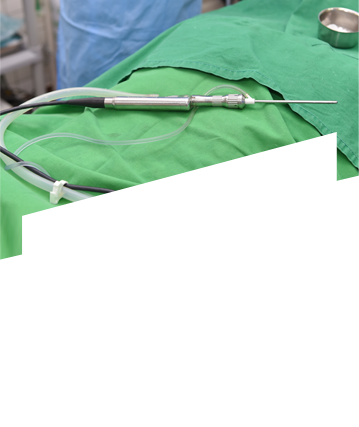

축농증 수술 네비게이션 장비 강남점 도입!

“실시간 교통상황보다 정확한 실시간 콧속상황”

네비게이션 축농증 수술 동영상으로 직접 확인해보세요

축농증 내시경 수술 과정

• 축농증 내시경 수술

수술 도구 삽입

내시경을 이용하여 염증제거